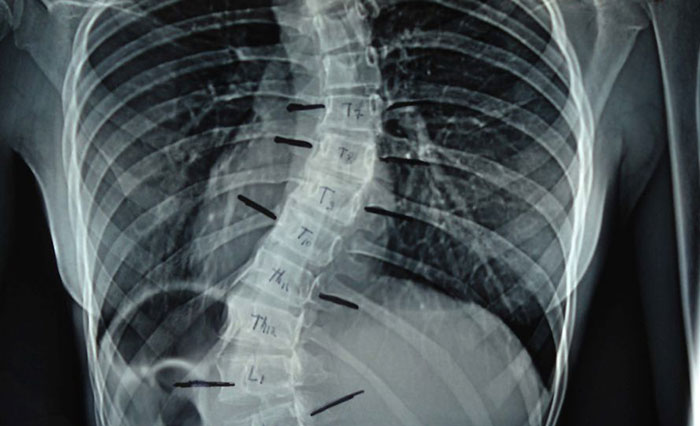

Определение уровня поражения проводится при помощи выявления имеющегося уровня искривления – на третьем этапе заболевания он варьирует в пределах от 26 до 50 градусов. Вторичным отклонением считают торсию – деформационный разворот отдельных позвонков, который также имеет свои показатели сложности.

- рентгеноскопии – процедура даст исчерпывающий ответ о состоянии позвоночного столба;